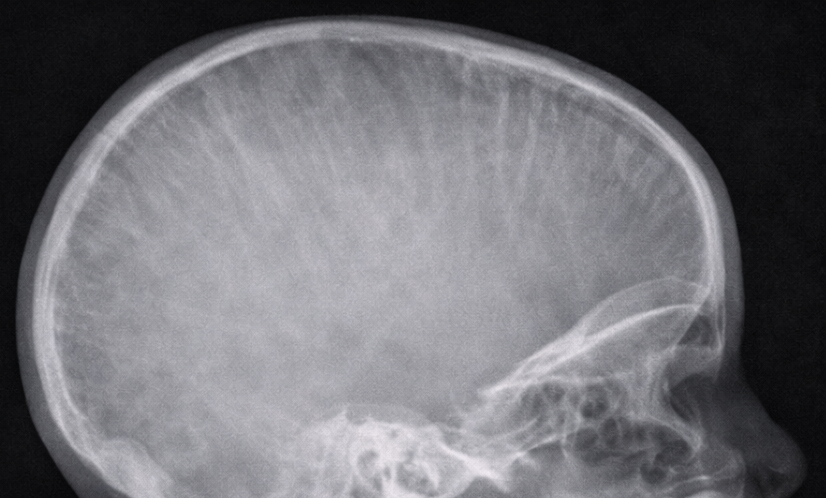

A lateral X-ray of the skull and nasopharynx was obtained to assess adenoid hypertrophy.

The radiograph demonstrated:

Prominent widening of the diploic spaces

Vertical striations giving a characteristic “hair-on-end” appearance

Soft tissue prominence in the nasopharyngeal region

These findings raised suspicion of marrow hyperplasia rather than isolated lymphoid hypertrophy.

Craniofacial involvement is rare and may present with airway obstruction, facial swelling, or radiological abnormalities. The “hair-on-end” appearance on skull radiographs is a classic but uncommon finding in modern clinical practice, reflecting marrow expansion secondary to increased erythropoietic demand [4].